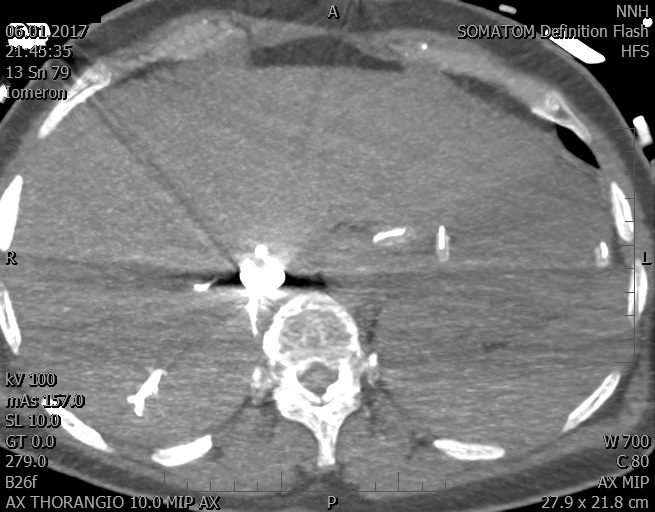

Video 1 - Akutní koronarografie prokázala normální nález na věnčitých tepnách s výjimkou suspekce na lehký spasmus na pravé koronární tepně.Echokardiograficky byla zjištěna těžká dysfunkce dilatované levé komory s nezvětšenou pravou komorou (video 2).

Video 2 - Echokardiograficky byla zjištěna těžká dysfunkce dilatační levé komory s nezvětšenou pravou komorou.Pro nejasnou příčinu zástavy jsme provedli i vyšetření výpočetní tomografií (CT), které vyloučilo plicní embolizaci (série 1 - soubory na konci článku). V den přijetí při přetrvávající oběhové nestabilitě byla nemocná opakovaně defibrilována pro fibrilaci komor se stabilizací rytmu po podání amiodaronu a mesocainu. Dle hemodynamických měření se jednalo o těžký kombinovaný šok. Vstupní laboratorní vyšetření bylo bez větších pozoruhodností. Posléze jsme doplnili anamnézu od příbuzných a zjistili, že pacientka užila do dvou hodin před srdeční zástavou první tabletu amoxicilinu na lehký respirační infekt. Při nevýtěžnosti vstupních vyšetření a nových anamnestických informacích jsme doplnili 14 hodin po kolapsu vyšetření koncentrace tryptázy v séru, která byla extrémně zvýšena (tabulka 2), což nás vedlo k podezření na anafylaxi.